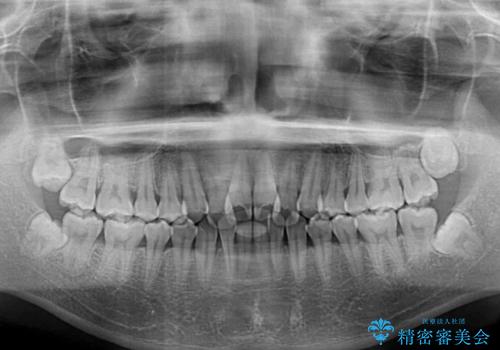

- 上下のクロスバイトと前歯のデコボコを気にして来院された患者様です。

インビザラインを用い、IPR(歯と歯の間を削る)と歯列全体を拡大させることで、歯並びを整えていくこととしました。

上下ともに歯列全体を後方に移動させるため、上下の親知らずを抜歯することとしました。